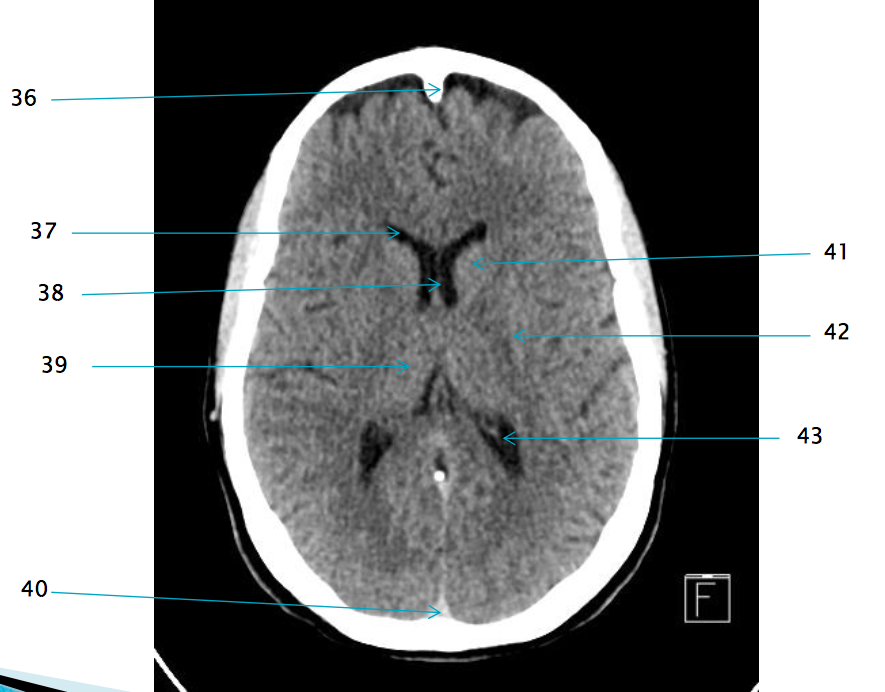

35

Superior sagittal sinus

32

R frontal lobe

37

Frontal horn of R lateral ventricle

38

Septum pellucidum